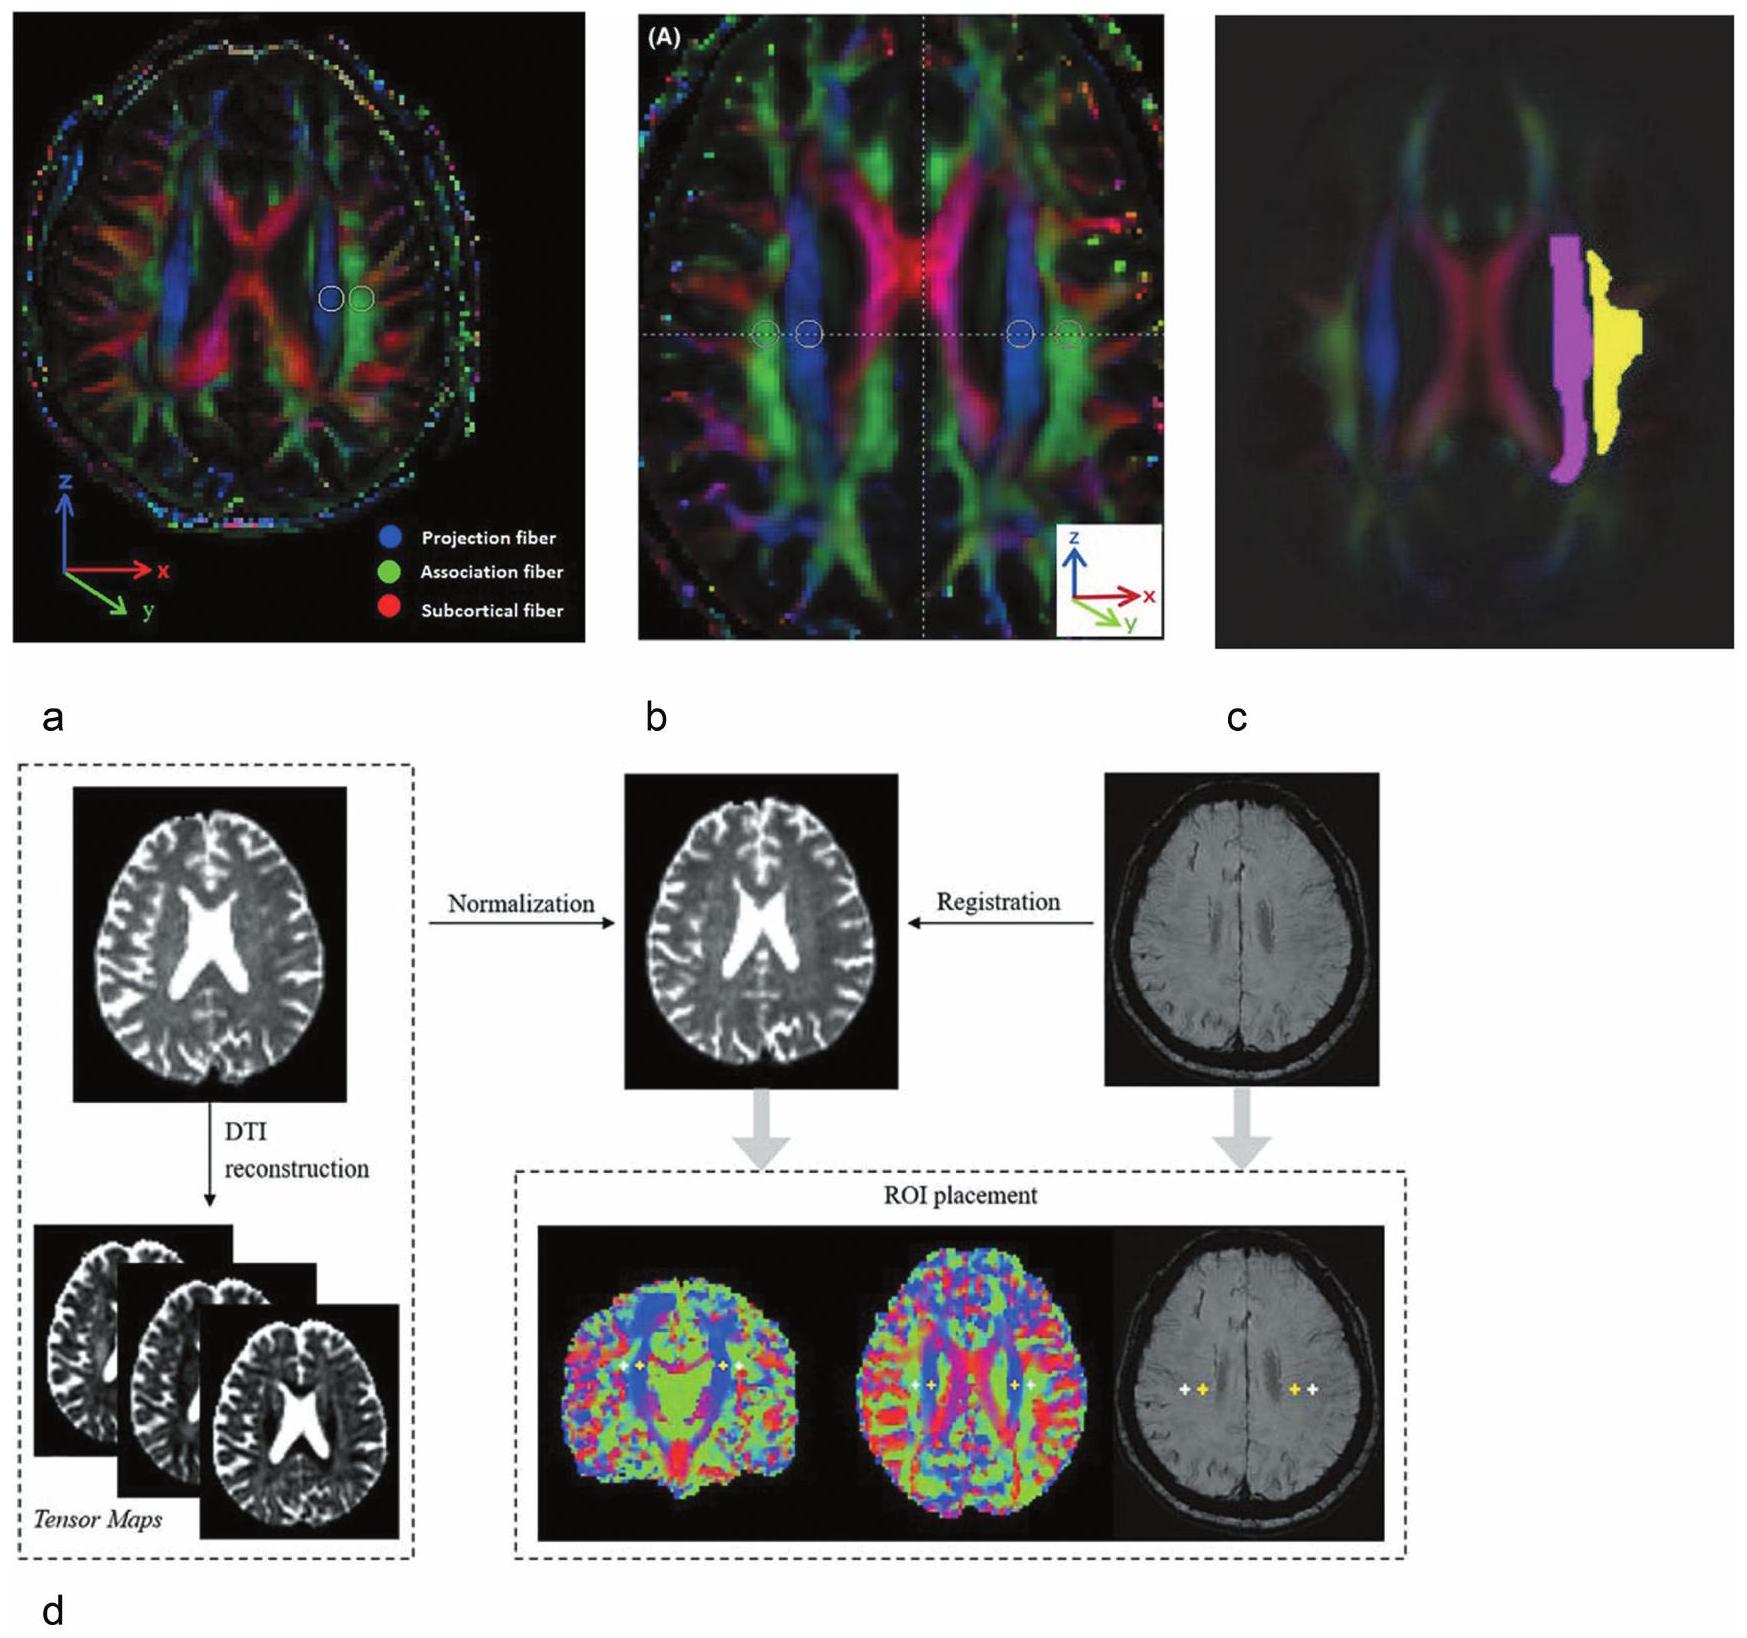

Placement of ROI

Reproducibility of ALPS method